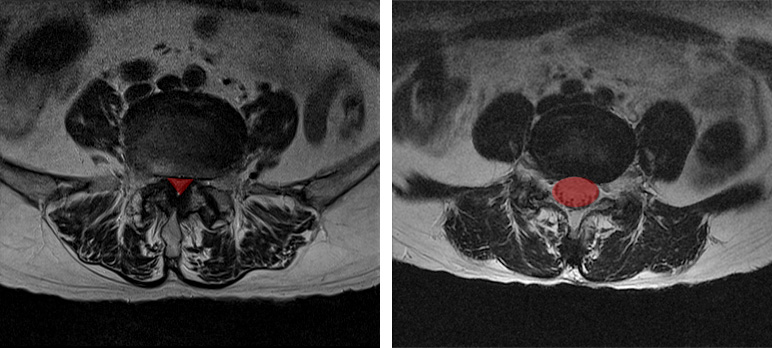

• 간격이 좁아진 디스크

• 정상 디스크

첫 번째 경우는 X-ray나 MRI 검사결과를 보고 디스크의 높이가 낮아진 것을 협착이라고 착각하는 경우입니다. 디스크가 퇴행되었거나 또는 디스크가 탈출되어 수핵이 빠져나가면 디스크의 높이가 낮아지는데, 디스크의 높이가 낮아지면 '디스크가 눌려서 압착되어 있으니까 이게 협착이구나' 하고 착각하게 되는 것 같습니다. 사실 협착이라는 단어는 일상생활에서 잘 쓰지 않는 단어이기 때문에 눌려서 압착되어 있는 걸 협착이라고 오해하는 것이죠. 그러나 디스크에 퇴행성 변화가 발생하여 디스크의 높이가 낮아진 것은 협착이 아니라, 그냥 허리디스크입니다. 협착이라는 것은 디스크를 옆에서 봤을 때 디스크가 눌린 게 아니고, 척추관이 좁아진 것을 말합니다.

• 좁아진 척추관

• 정상 척추관

척추관이 좁아지게 되면 MRI로도 많이 좁아진 게 보이며, 반대로 협착증이 아닌 경우에는 MRI 상으로도 공간이 넓습니다. 따라서 단순히 디스크의 높이가 낮아진 것을 보고 이걸 협착이라고 착각하시면 안 됩니다.